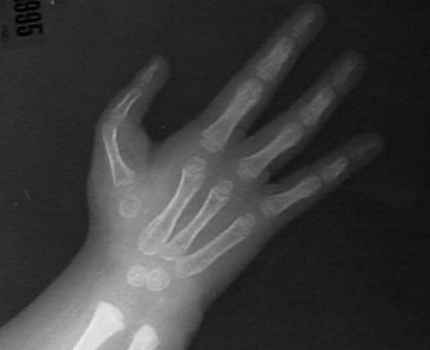

Radiographs

HL4